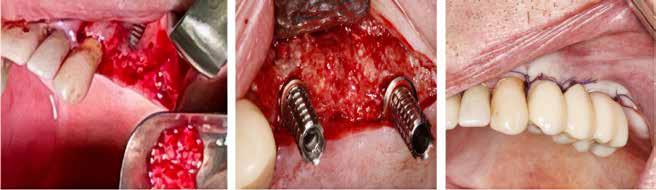

Klik ind på Tandlægebladet.dk og opret en reklamation, så sørger vi for, at bladet lander i din postkasse.

Klik ind på Tandlægebladet.dk og vælg om os

BAGGRUND – Transverselle okklusionsafvigelser kombineret med en vækstbetinget kæbedeformitet korrigeres sædvanligvis ved en sektioneret Le Fort 1-osteotomi eller kirurgisk assisteret ganeekspansion. Ved ekstreme transverselle skeletale diskrepanser mellem maksillen og mandiblen kan der være indikation for transversel udvidelse af mandiblen ved hjælp af mandibulær midtlinjeosteotomi eller mandibulær midtlinjedistraktionsosteogenese.

PATIENTTILFÆLDE – En 15-årig dreng med infantil autisme blev henvist fra Hjørring Kommunes Tandpleje til Kæbekirurgisk Afdeling, Aalborg Universitetshospital, for ortodontisk-kirurgisk behandling af et stort horisontalt maksillært overbid uden kontakt på nogen af tænderne. Den vækstbetingede kæbedeformitet blev korrigeret ved hjælp af ortodonti og mandibulær midtlinjedistraktionsosteogenese efterfulgt af en sektioneret Le Fort I-osteotomi og bilateral sagittal splitosteotomi.

KONKLUSION – Mandibulær midtlinjedistraktionsosteogenese er en forudsigelig behandlingsmodalitet til transversel udvidelse af mandiblen. Imidlertid er behandlingen forbundet med en betydelig risiko for recidiv samt biologiske og tekniske komplikationer, hvorfor mandibulær midtlinjedistraktionsosteogenese udelukkende anbefales til korrektion af ekstreme vækstbetingede transverselle okklusionsafvigelser.

EMNEORD Jaw abnormalities | malocclusion | orthodontics | orthognathic surgery

PERNILLE SAGBAKKEN, tandlæge, Odontologisk Institut, Det Sundhedsvidenskabelige Fakultet, Københavns Universitet

ANNETTE DALGAARD KJELLERUP, specialtandlæge i ortodonti, Kæbekirurgisk Afdeling, Aalborg Universitetshospital